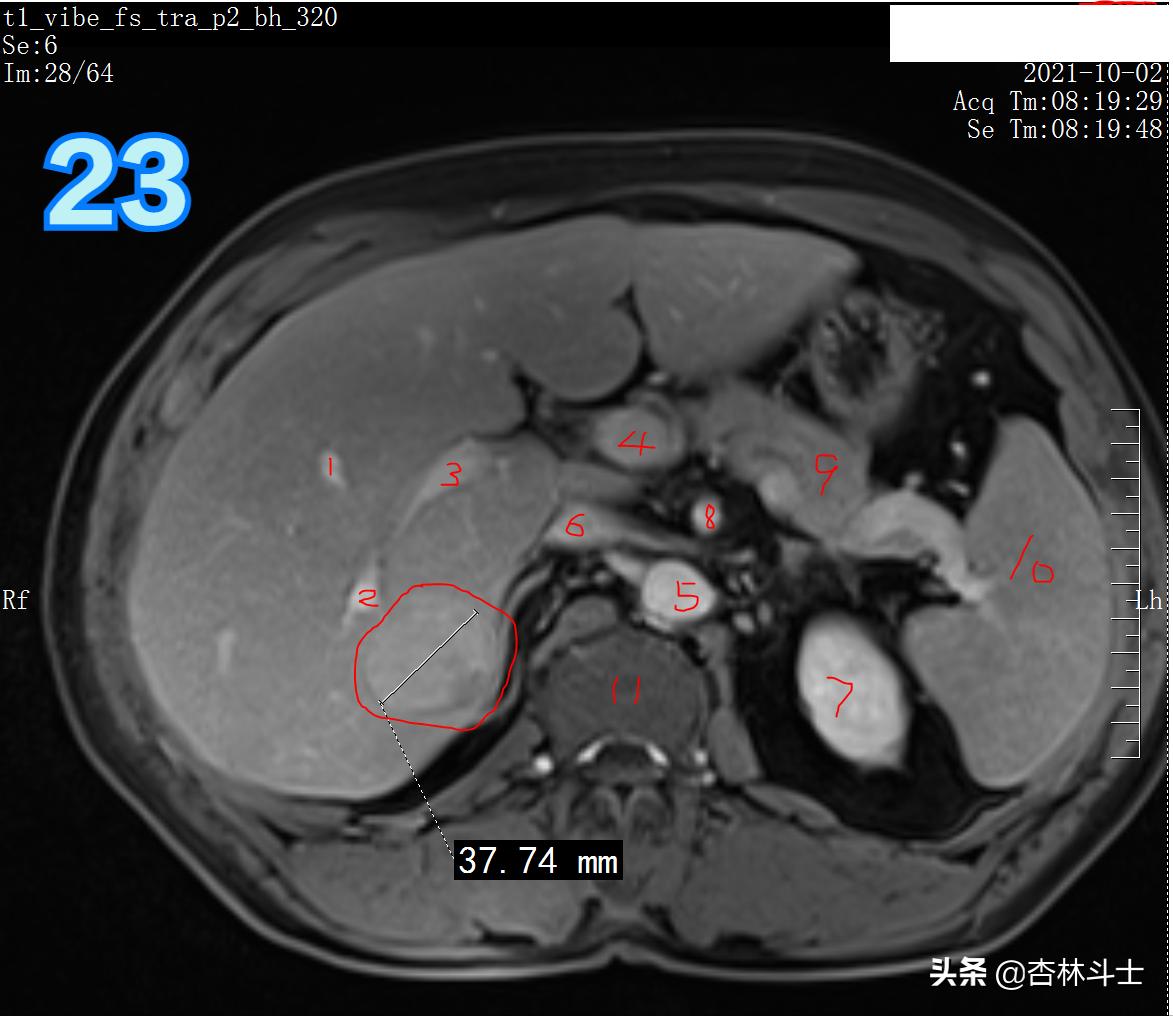

T1压脂 门静脉期

图23 1、肝静脉分支 2、门静脉分支 3、门静脉右支 4、门静脉主干 5、腹主动脉 6、下腔静脉 7 、左肾 8、肠系膜上动脉 9、胰腺 10、脾

图23-24 门静脉期,病灶强化程度略减低,但较周围的肝实质仍呈高信号。